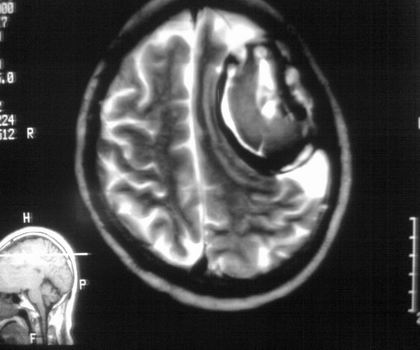

以下是引用影像孺子牛在2008-4-29 21:20:00的发言:[br]首先病变定位在脑外,根据ct密度及mri信号特征考虑慢性硬膜下血肿不连续环形钙化。

以下是引用周战梅在2008-4-29 23:12:00的发言:[br]脑外病变,蛛网膜下腔增宽,囊壁点状、环形钙化,增强扫描呈不均匀环状强化,考虑为囊性脑膜瘤可能性大,慢性脓肿、血肿机化、胆脂瘤不能除外。